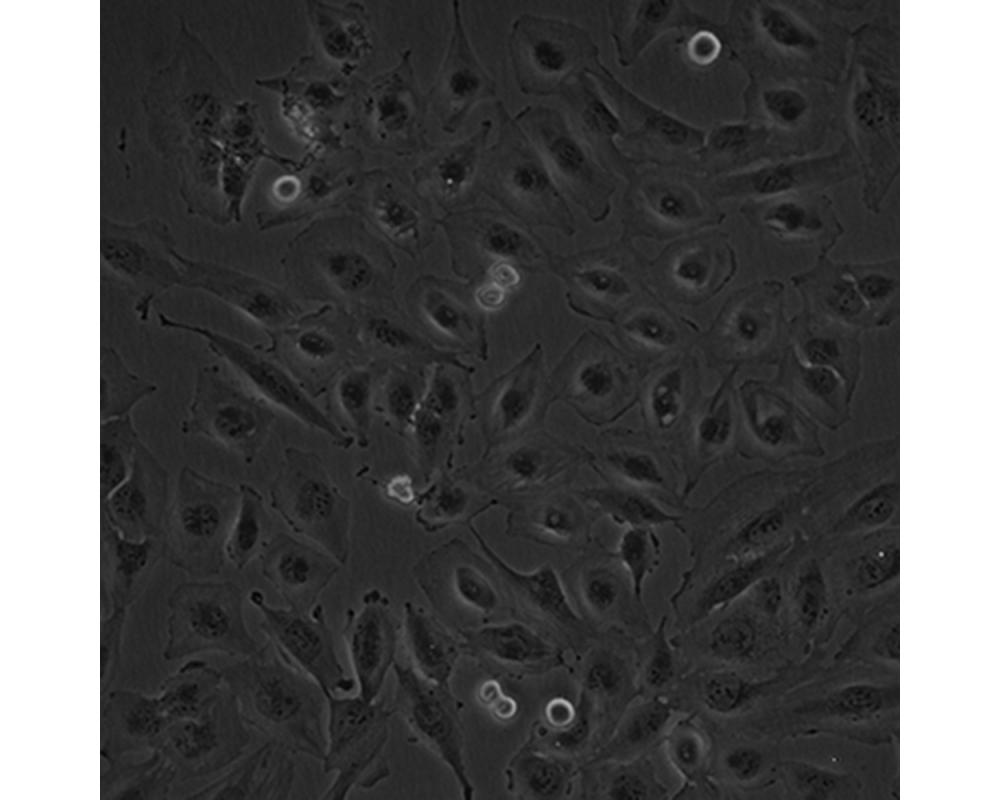

中文名稱 人腦髓母細胞瘤細胞

組織來源 成神經管細胞瘤;男性

形態特征 多邊形

生長特性 貼壁生長

特征特性 該細胞是1985年由Jacobsen PF建立的,源自一名4歲大的兒童的后顱窩腫瘤的活檢組織,未檢出神經元和膠質分化的特征;可用作轉染宿主。